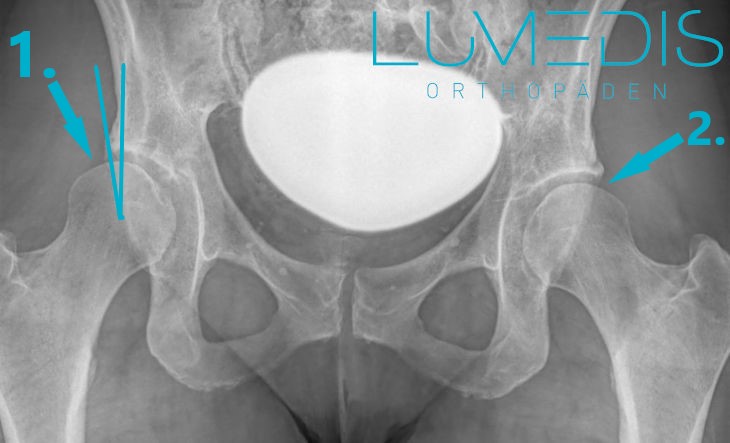

Röntgenbild eine Hüftarthrose

Röntgenbild a.p. einer Hüftdysplasie

Röntgenbild einer Hüftdysplasie rechts

Ein wichtiges Element stellt die Bildgebung in Form einer Röntgen-Untersuchung dar, da hier die Schädigung des Gelenkknorpels sowie der Gelenkknochen durch typische Arthrosezeichen sichtbar gemacht werden kann.

Im Röntgenbild einer Hüftarthrose zeigen sich typische Veränderungen, die den Fortschritt der Erkrankung und die Schädigung des Gelenks visualisieren.

Zu den häufigsten Merkmalen zählen:

Das Röntgenbild zeigt somit die strukturellen Veränderungen, die zur Schmerzsymptomatik und Bewegungseinschränkung führen, und hilft bei der Planung der individuellen Therapie